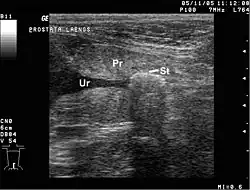

Urología

Mide la cantidad de fluido retenido en la vejiga del paciente.

Sonogramas pélvicos muestran los órganos de la región pélvica: útero, ovarios, vejiga urinaria, próstata y testículos.

Existen dos métodos para realizar una ecografía pélvica: externa o interna. La ecografía pélvica interna se realiza transvaginalmente (en una mujer) o transrectal (en un hombre).